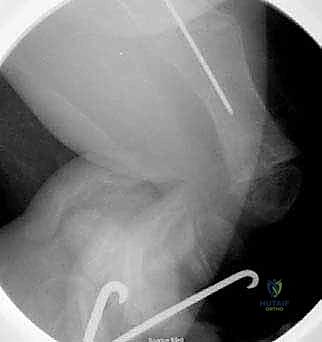

الخطوة الأولى: التخطيط الجراحي الدقيق (Pre-operative Planning)

قبل العملية، يقوم الدكتور هطيف بإجراء دراسة شاملة لصور الأشعة السينية (X-rays) المأخوذة بدقة، لحساب زوايا التقوس بدقة متناهية، وتحديد نقاط بضع العظم (أماكن القص)، واختيار الحجم والطول المناسبين للمسمار التلسكوبي.

يتم إجراء العملية تحت التخدير العام. يتم وضع الطفل على طاولة العمليات الشفافة للأشعة، ويتم استخدام جهاز الأشعة السينية المستمر (C-arm) لضمان الدقة المطلقة خلال كل ثانية من العملية.

بعد تقويم العظم وجعله مستقيماً كحبات المسبحة على خيط، يتم إدخال السلك الدليلي (Guide Wire). ثم يتم إدخال الجزء الخارجي (الأنثوي) من المسمار التلسكوبي وتثبيته في الجزء العلوي من العظم (Epiphysis).

بعد ذلك، يتم إدخال الجزء الداخلي (الذكري) من المسمار عبر الجزء السفلي من العظم وتثبيته في المشاشة السفلية. هذا التصميم العبقري يضمن حماية العظم بالكامل من الداخل.